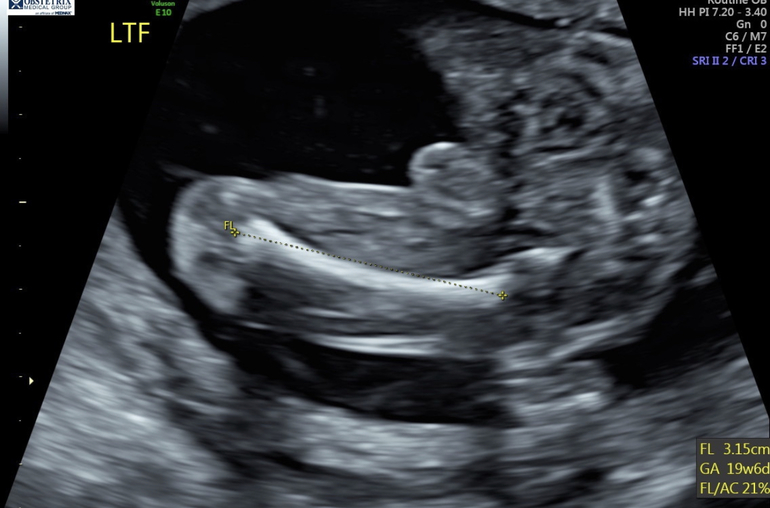

В отчете указана длина 28.6 мм (судя по фотографиям это длина правой бк), все калькуляторы пишут, что сроку не соответствует. Длина левого бедра судя по фотографиям 31.5, что является прям абсолютной нормой для 20 недель.

Левая нога:

Правая: